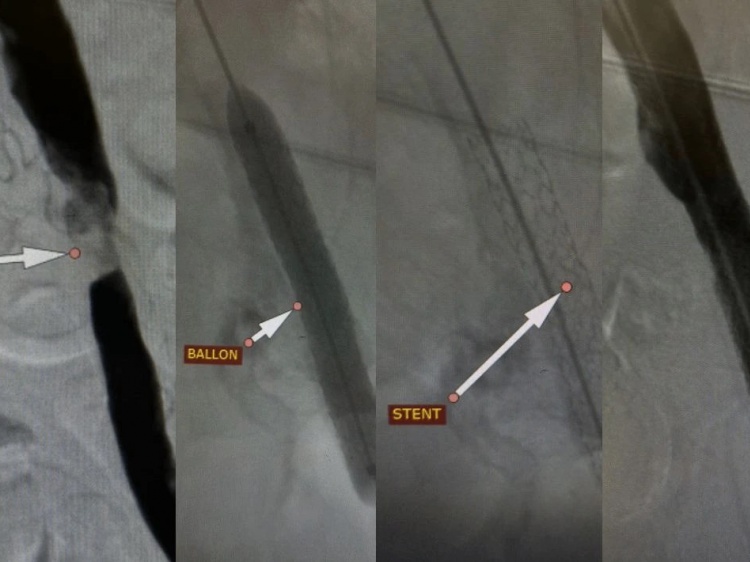

В Волгоградской области медики спасли ногу пациенту с серьезной патологией. Как рассказали Волжский.ру в комитете здравоохранения, 53-летний мужчина, поступивший в больницу № 25, жаловался на невозможность наступать на больную конечность, сильные боли, нарушающие сон, холодность и бледность кожи ноги. Во время обследования выявили значительное сужение артерий ноги – «ишемию покоя». Такое состояние опасно быстрым развитием необратимых изменений тканей вплоть до образования язв, некрозов и гангрены, приводящих к возможной ампутации конечности. Традиционные методы хирургического вмешательства были противопоказаны из-за тяжелого состояния сосудов и распространенности поражения.